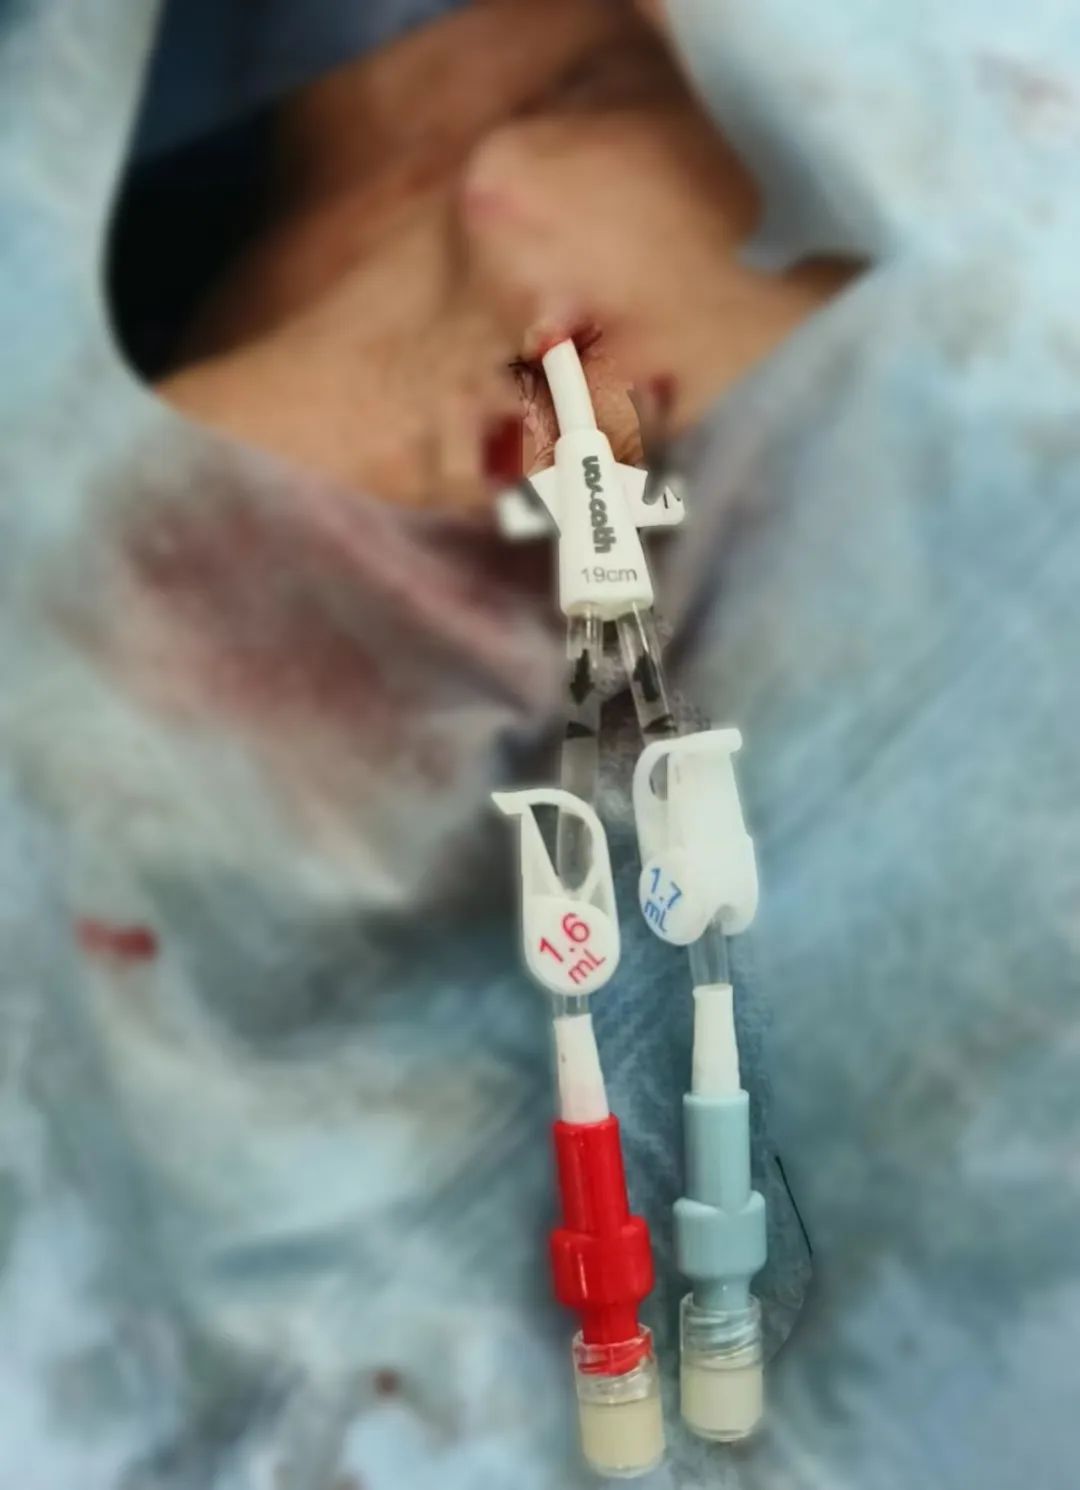

介入技术也成为该领域的重要保障措施。与传统置管相比,介入下置管更为安全精准及可视化,导丝精准进入,减少血管损伤及防止误入分支静脉,对血管基础较差,血管狭窄等血管条件复杂情况的治疗,具有得天独厚的优势,是未来发展重要方向之一。

半永久导管又叫做带涤纶套(cuff)中心静脉导管,它是血液透析用血管通路的一种,留置时需建立一段皮下隧道,cuff通常放置于距离导管皮肤出口2厘米处的皮下隧道内,数日后皮下组织会长入涤纶套内。相比临时导管,cuff管使用时间长,感染率低,是一种安全有效,快速建立血管通路的方法。